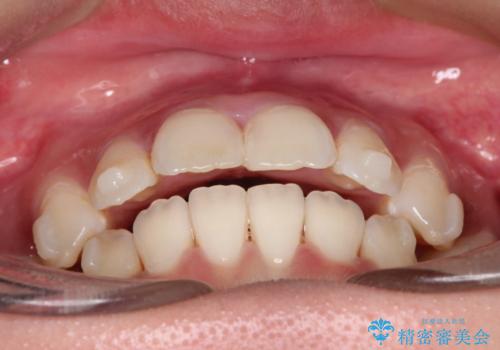

【インビザライン】シザーズバイト、抜歯矯正

- オープンバイトを主訴に来院された患者様です。

抜歯を行うことで、インビザラインを用いて前歯を下げることができ、同時にオープンバイトを改善することができました。

今回はインビザラインのみで治療を終了することができました。